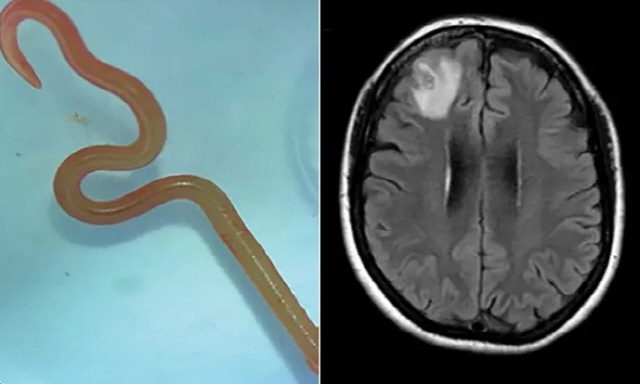

결국 신경외과의 하리 프리야 반디 박사가 수술을 진행했고, 충격적인 장면을 처음 목격했다. 여성의 뇌에서 8㎝ 길이의 기생충을 꺼냈을 뿐만 아니라, 그 벌레가 살아서 꿈틀대고 있었던 것이다.

호주 연방과학산업연구기구(CSIRO)는 이 기생충을 '오피다스카리스 로베르시'라는 회충으로 확인했다. 이 회충은 주로 비단뱀 체내에서 발견되며, 사람 몸에서 확인된 건 이번이 처음이라고 가디언은 전했다.